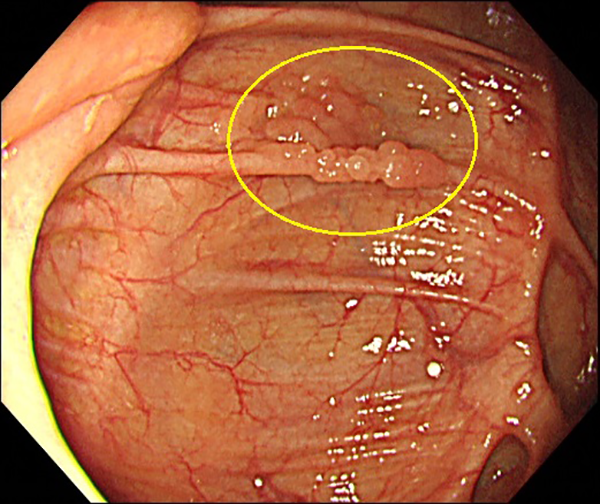

④盲腸癌(側方発育型腫瘍(LST))

1. 大腸癌検診の便潜血陽性で内視鏡検査を施行、盲腸のヒダ上に小さな不整隆起を認めます。

2. NBI画像処理で側方発育型腫瘍(顆粒型)径20mmを認めます。内視鏡的粘膜切除術で治癒、粘膜内癌と診断されました。